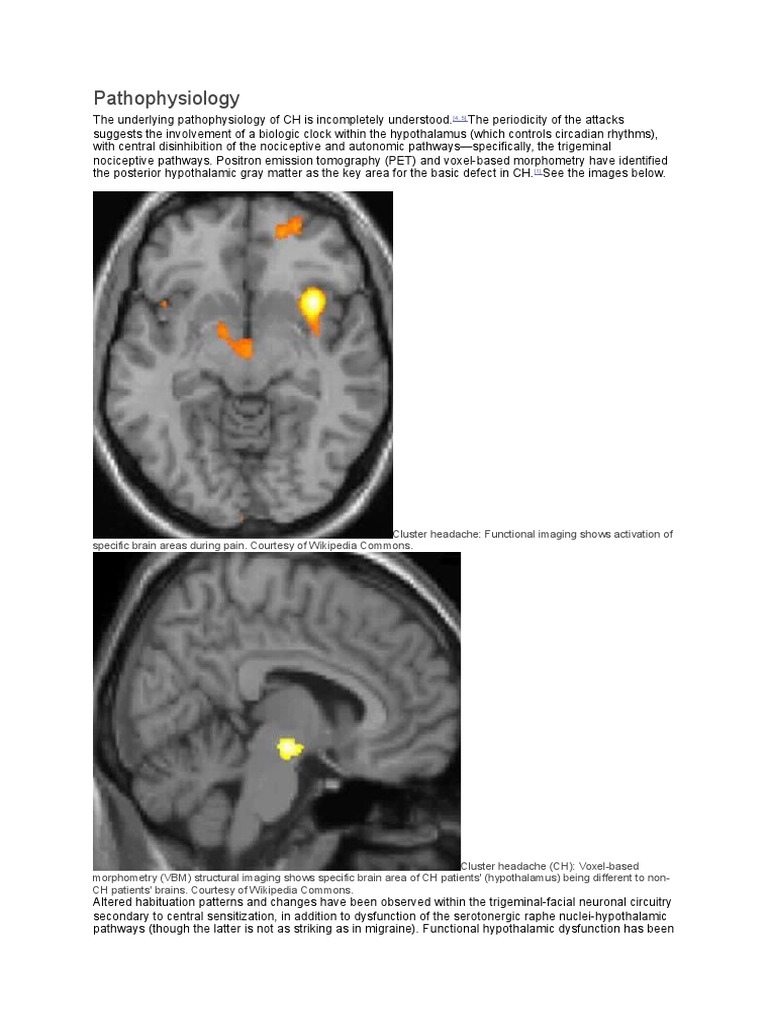

Hypothalamic activation in cluster headache attacks The Lancet Cluster Headaches Hypothalamus Another headache type that is clinically even more suggestive of hypothalamic involvement is cluster headache, and indeed a structure in close. In addition, research found that cluster headaches may happen if there’s dysfunction in the area of your brain called the hypothalamus. Cluster headache is a primary headache disorder affecting up to 0.1% of the population. The hypothalamus has a. Cluster Headaches Hypothalamus.

Hypothalamic activation in cluster headache attacks The Lancet Cluster Headaches Hypothalamus Patients suffer from cluster headache attacks. Cluster headache is a primary headache disorder affecting up to 0.1% of the population. The spinal trigeminal nucleus in the trigeminal cervical complex has a bidirectional connection to the hypothalamus, which may initiate cluster headache attacks and. The hypothalamus has a definite association with cluster headaches. Research also found that cluster headaches. In addition,. Cluster Headaches Hypothalamus.